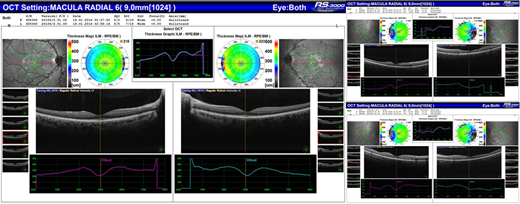

Methods:The study included 108 eyes of 54 SCD patients as well as 110 eyes of 55 healthy subjects with no ocular pathology as a control group. A complete ophthalmologic examination was performed. Pupillary dilation was induced and macular sections were obtained with spectral domain OCT. Macular sections were evaluated according to the ETDRS map. Inner and outer retinal thicknesses were measured using the software in the device.

Results:Foveal splaying, temporal thinning of retinal thickness, and vascular tortuosity were found to be significantly higher in the patient group than the control group (p <0.0001 for all three parameters)(Figure-1).The foveal diameter (1592.39 ± 175.56 μ) was significantly increased in the patient group compared to the control group (1391.01 ± 175.56 μ) (p<0.0001) and the foveal depth was significantly decreased in the patient group (121.15 ± 26.83 μ) compared to the control group (146.1 ± 12.25 μ) (p<0.0001). The mean total retinal thickness was 253.53 ± 22.31 μ in the patient group and 261.03 ± 18.48 μ in the control group and the difference was statistically significant (p = 0.007). Likewise, central retinal thickness was significantly decreased in the patient group (219.35 ± 10.53 μ) compared to the control group (235.32 ± 12.51 μ) (p <0.0001).